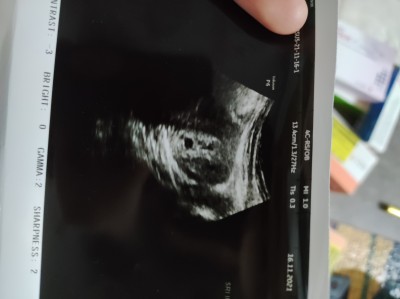

Ultrasona bakar mısınız?

burada 2 kese mi var bana mı öyle geliyor

Bugün kanamam olduğu için acilden gittim bir şey demedi ama pek hoşuma gitmedi doktor ultrasona pek bakmadi

Anladım canım 1.hafta sonra gidersen daha net belli olur.ama polikliniğe git

Alttaki kese, üstteki kanama alanına benziyor